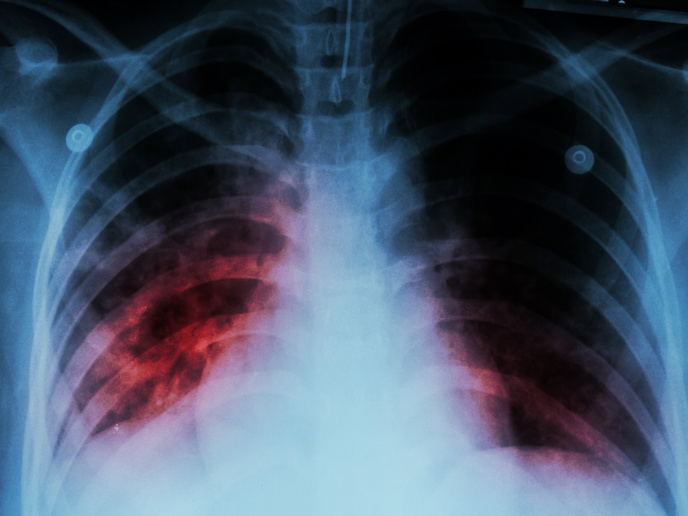

L'imagerie par résonnance magnétique (IRM) peut détecter et diagnostiquer des pathologies dans la plupart des tissus de notre corps. Un nouveau simulateur IRM qui recrée le mouvement du cœur et de la respiration contribuera à optimiser les algorithmes et la formation du nouveau personnel.

L'IRM n'utilise pas de rayonnements ionisante, il s'agit donc d'une méthode très sure et non-invasive pour déterminer les propriétés statiques et dynamiques des tissus biologiques. Avec le soutien de l'UE au nom du projet MRISIMUL(s’ouvre dans une nouvelle fenêtre) («Enhanced MRI physics simulator»), des scientifiques ont mis au point un outil de simulation réaliste qui fonctionne sur un ordinateur unique. L'idée était d'intégrer les aspects réalistes d'une expérience d'IRM afin de comprendre les mécanismes de génération d'artéfact lors de l'IRM cardiovasculaire. Cela permettra de mieux examiner les protocoles sans avoir besoin d'expériences humaines ou animales coûteuses plus compliquées. Les scientifiques ont mis au point une plateforme MATLAB qui soutient le développement de séquences d'impulsions d'IRM personnalisées et leur application à modeler des objets. MRISIMUL exploite la simulation Bloch, le moyen le plus précis pour étudier l'effet de la séquence d'impulsion sur la magnétisation. Suite à une analyse de puissance computationnelle, l'équipe a déterminé que des temps d'exécution très longs (soit plusieurs jours) étaient nécessaires même à l'aide d'un PC de pointe. Les chercheurs ont remplacé l'approche fondée sur le processeur (CPU) par un grand nombre de noyaux de traitement intégrés avec un processeur graphique (GPU), une fois de plus sur un seul ordinateur. Aujourd'hui, les services de base exigeants (noyau) sont exécutés parallèlement au sein de l'environnement GPU à une vitesse d'environ 228 fois comparé au traitement en série avec un CPU. Cela signifie, par exemple, qu'au lieu de 5 journées entières (120 heures), une simulation nécessite maintenant environ une demi-heure. Dans des systèmes à multi-nœuds, multi-GPU, MRISIMUL a démontré une performance presque extensible de façon linéaire avec un nombre accru de cartes GPU disponibles. L'équipe a désormais mis au point un modèle 3D du cœur et du torse humains qui simule les mouvements adéquats, dont la respiration, le cœur et le simple flux. Le modèle peut être installé à partir du site web du projet. Là, les utilisateurs trouveront également une distribution spatiale «floue» du cerveau, comprenant 11 types de tissus. MRISIMUL a été accueilli chaleureusement par la communauté scientifique, dont sa première description est apparue dans la revue Journal of Cardiovascular Magnetic Resonance, obtenant la mention d'«accessibilité renforcée» en moins d'un mois depuis sa publication. Le projet ouvre également la voie pour l'extension à d'autres domaines biomédicaux. Les citoyens de l'UE peuvent s'attendre rapidement à de meilleurs diagnostics et soins pour une variété de maladies.